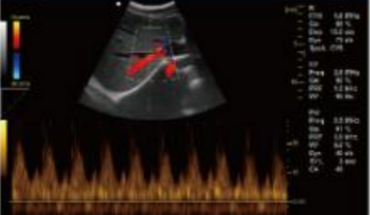

- B+CF (Dual Images)

- B+CF/DPDI+PW (Triplex)